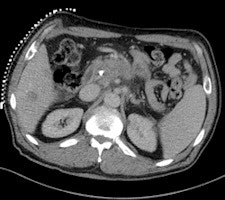

In nine cases -- eight soft-tissue, one liver -- MR fluoroscopy was used to define the entry site, and the physician used a fingertip or water-filled syringe as a marker. In 29 cases -- 11 soft-tissue, 18 liver -- a marker capsule (Adalat, Bayer) was affixed to the supposed entry side with adhesive tape, and the position was corrected after application of conventional sequences. After sterile draping, administration of local anesthesia and skin incision, an MR-compatible puncture needle (14-18 G) was placed subcutaneously outside the magnet.